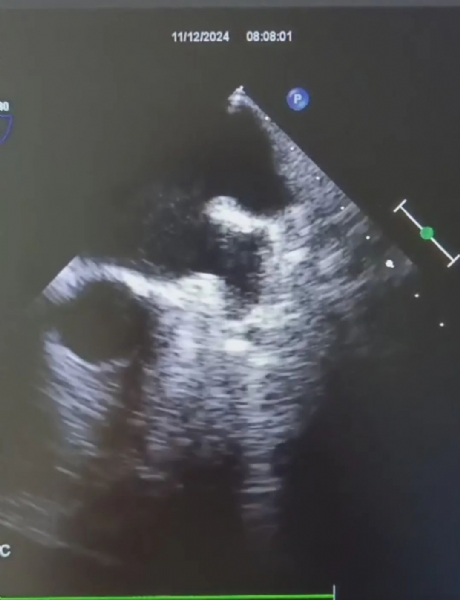

近日,我院超声科又顺利完成一例经食管超声心动图(transesophageal echocardiography,TEE)检查,TEE是将特殊的食管探头置于食管或胃底,从心脏后方向前扫查心脏。可以避免肺气和胸壁的干扰,由于探头紧邻左房,能清晰显示心脏内部的细微结构,在诊断左心耳血栓、卵圆孔未闭、感染性心内膜炎、人工瓣膜并发症等方面具有更高的准确性。